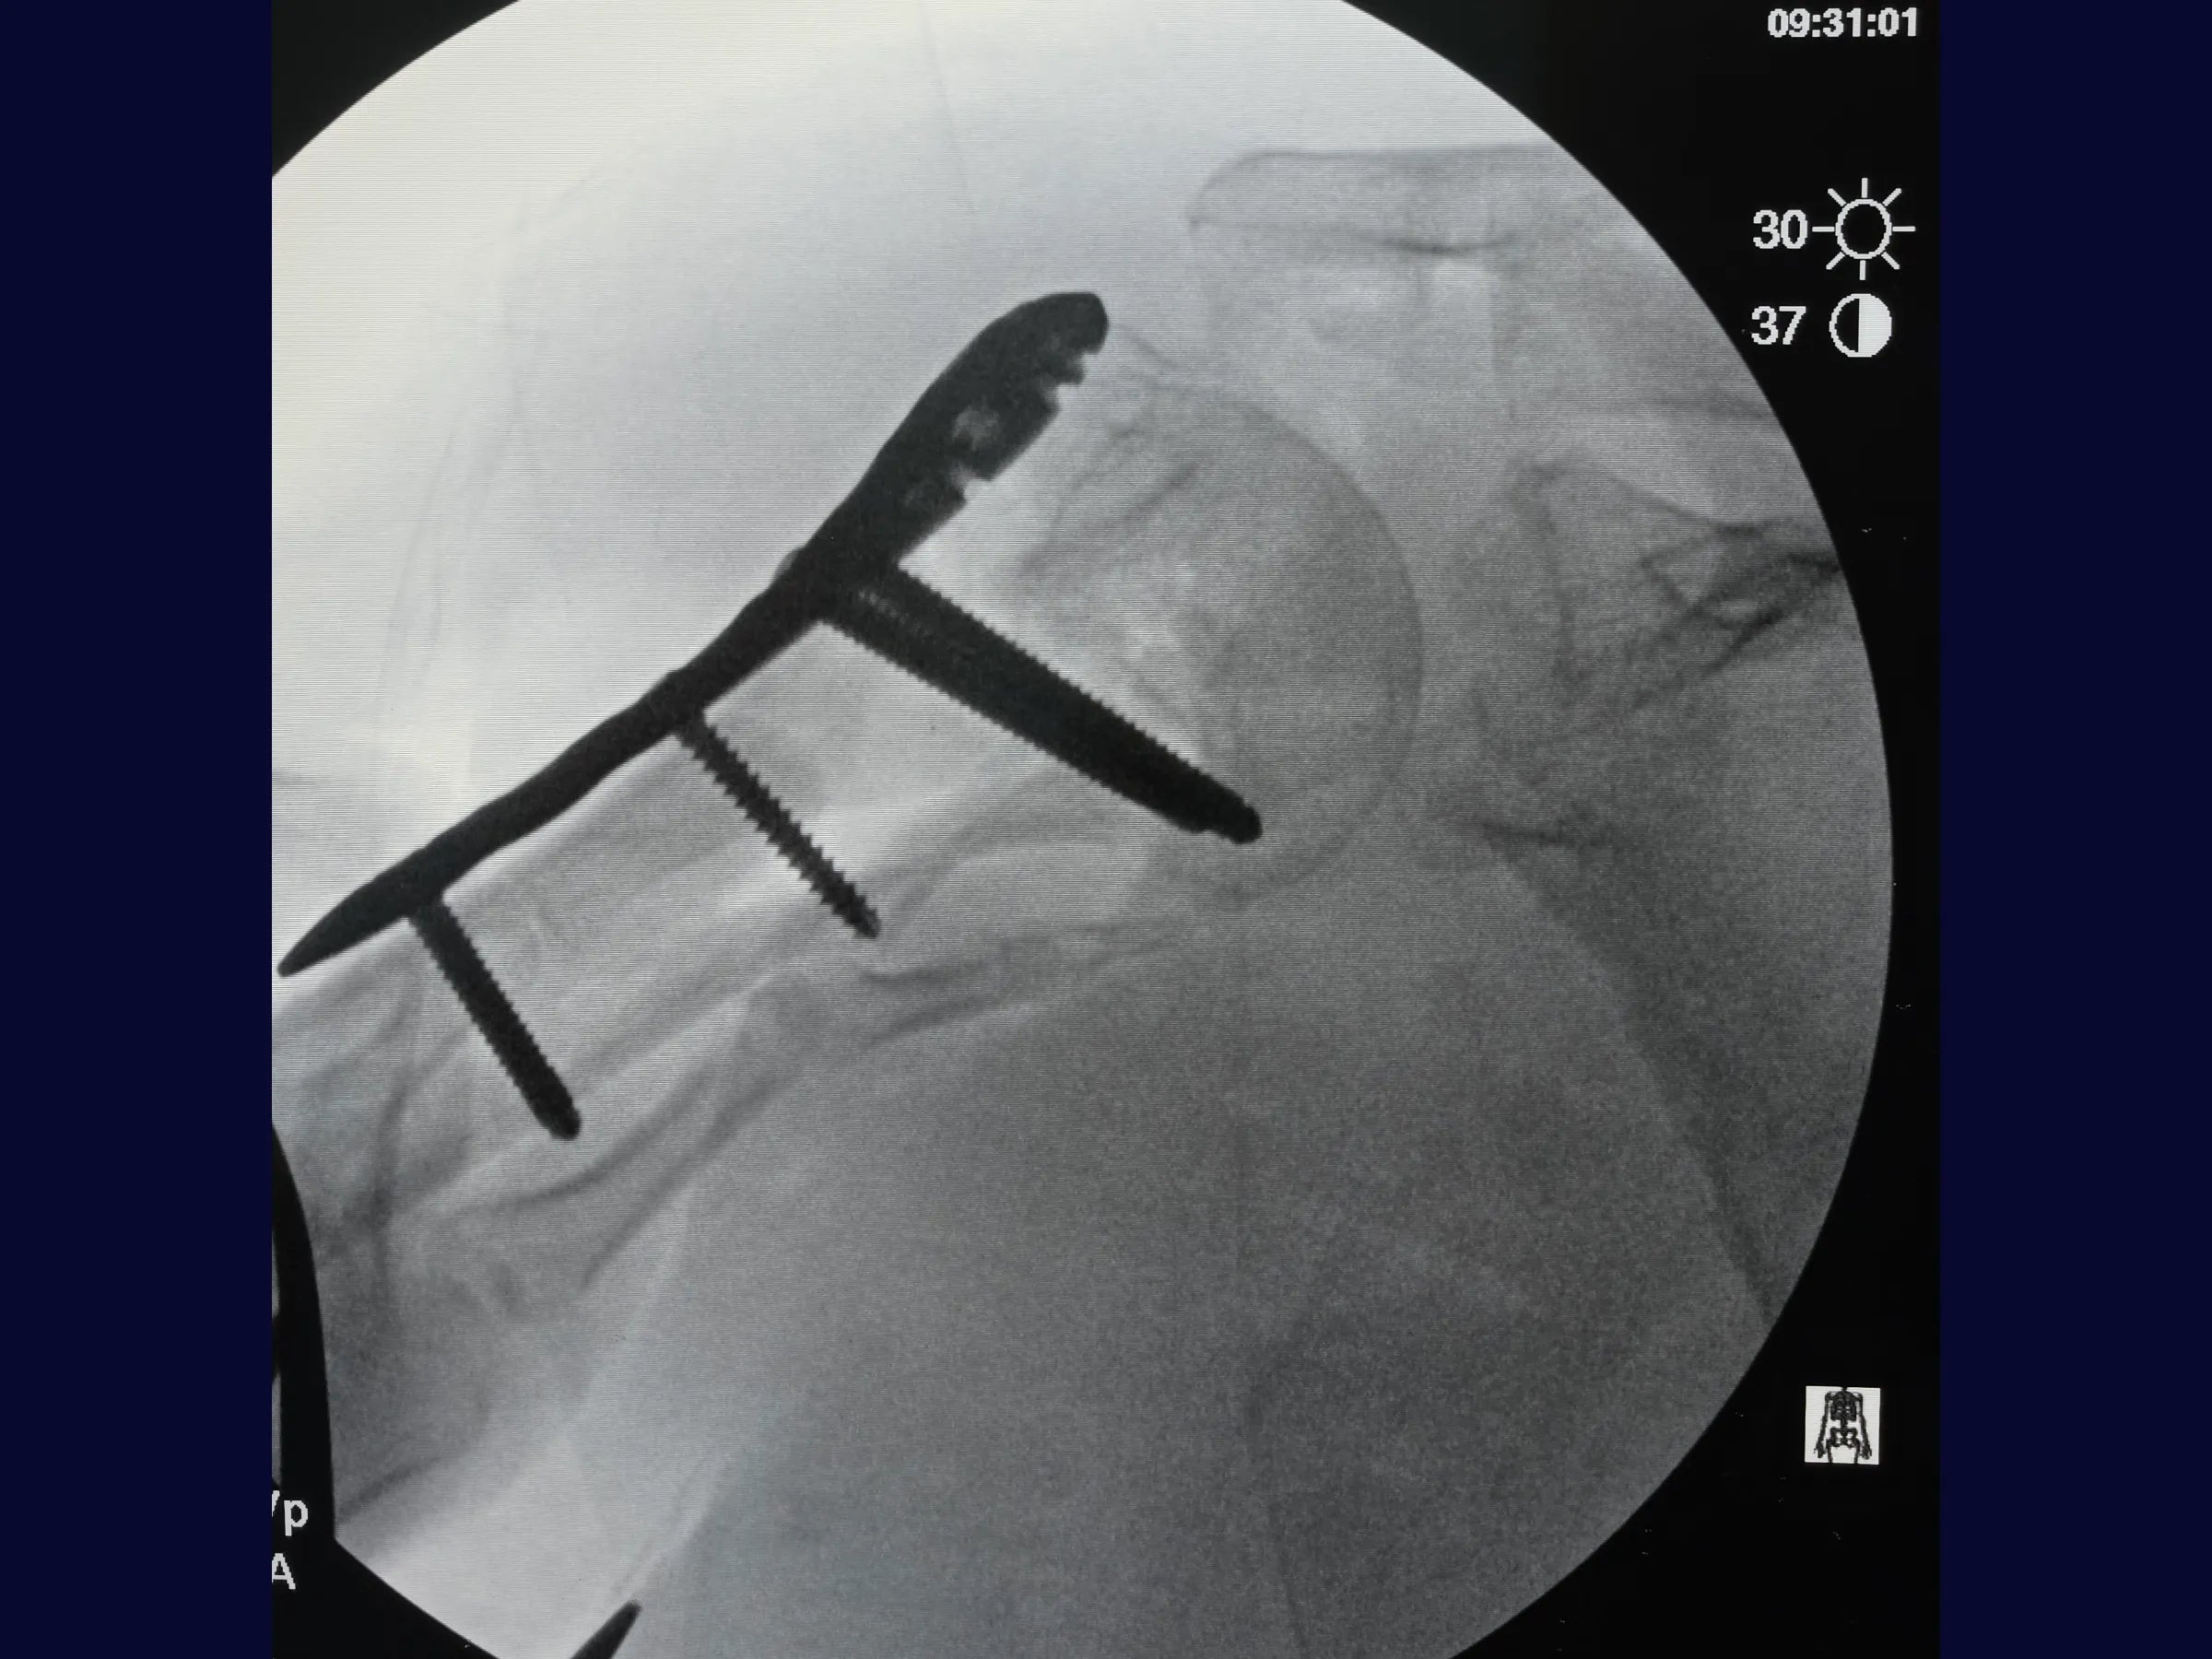

- Fixação com placa bloqueada e parafusos do calcar;

- Controle Radiográfico e Ajustes Finais: Correção de cisalhamento e simetria com reposicionamento de parafusos.